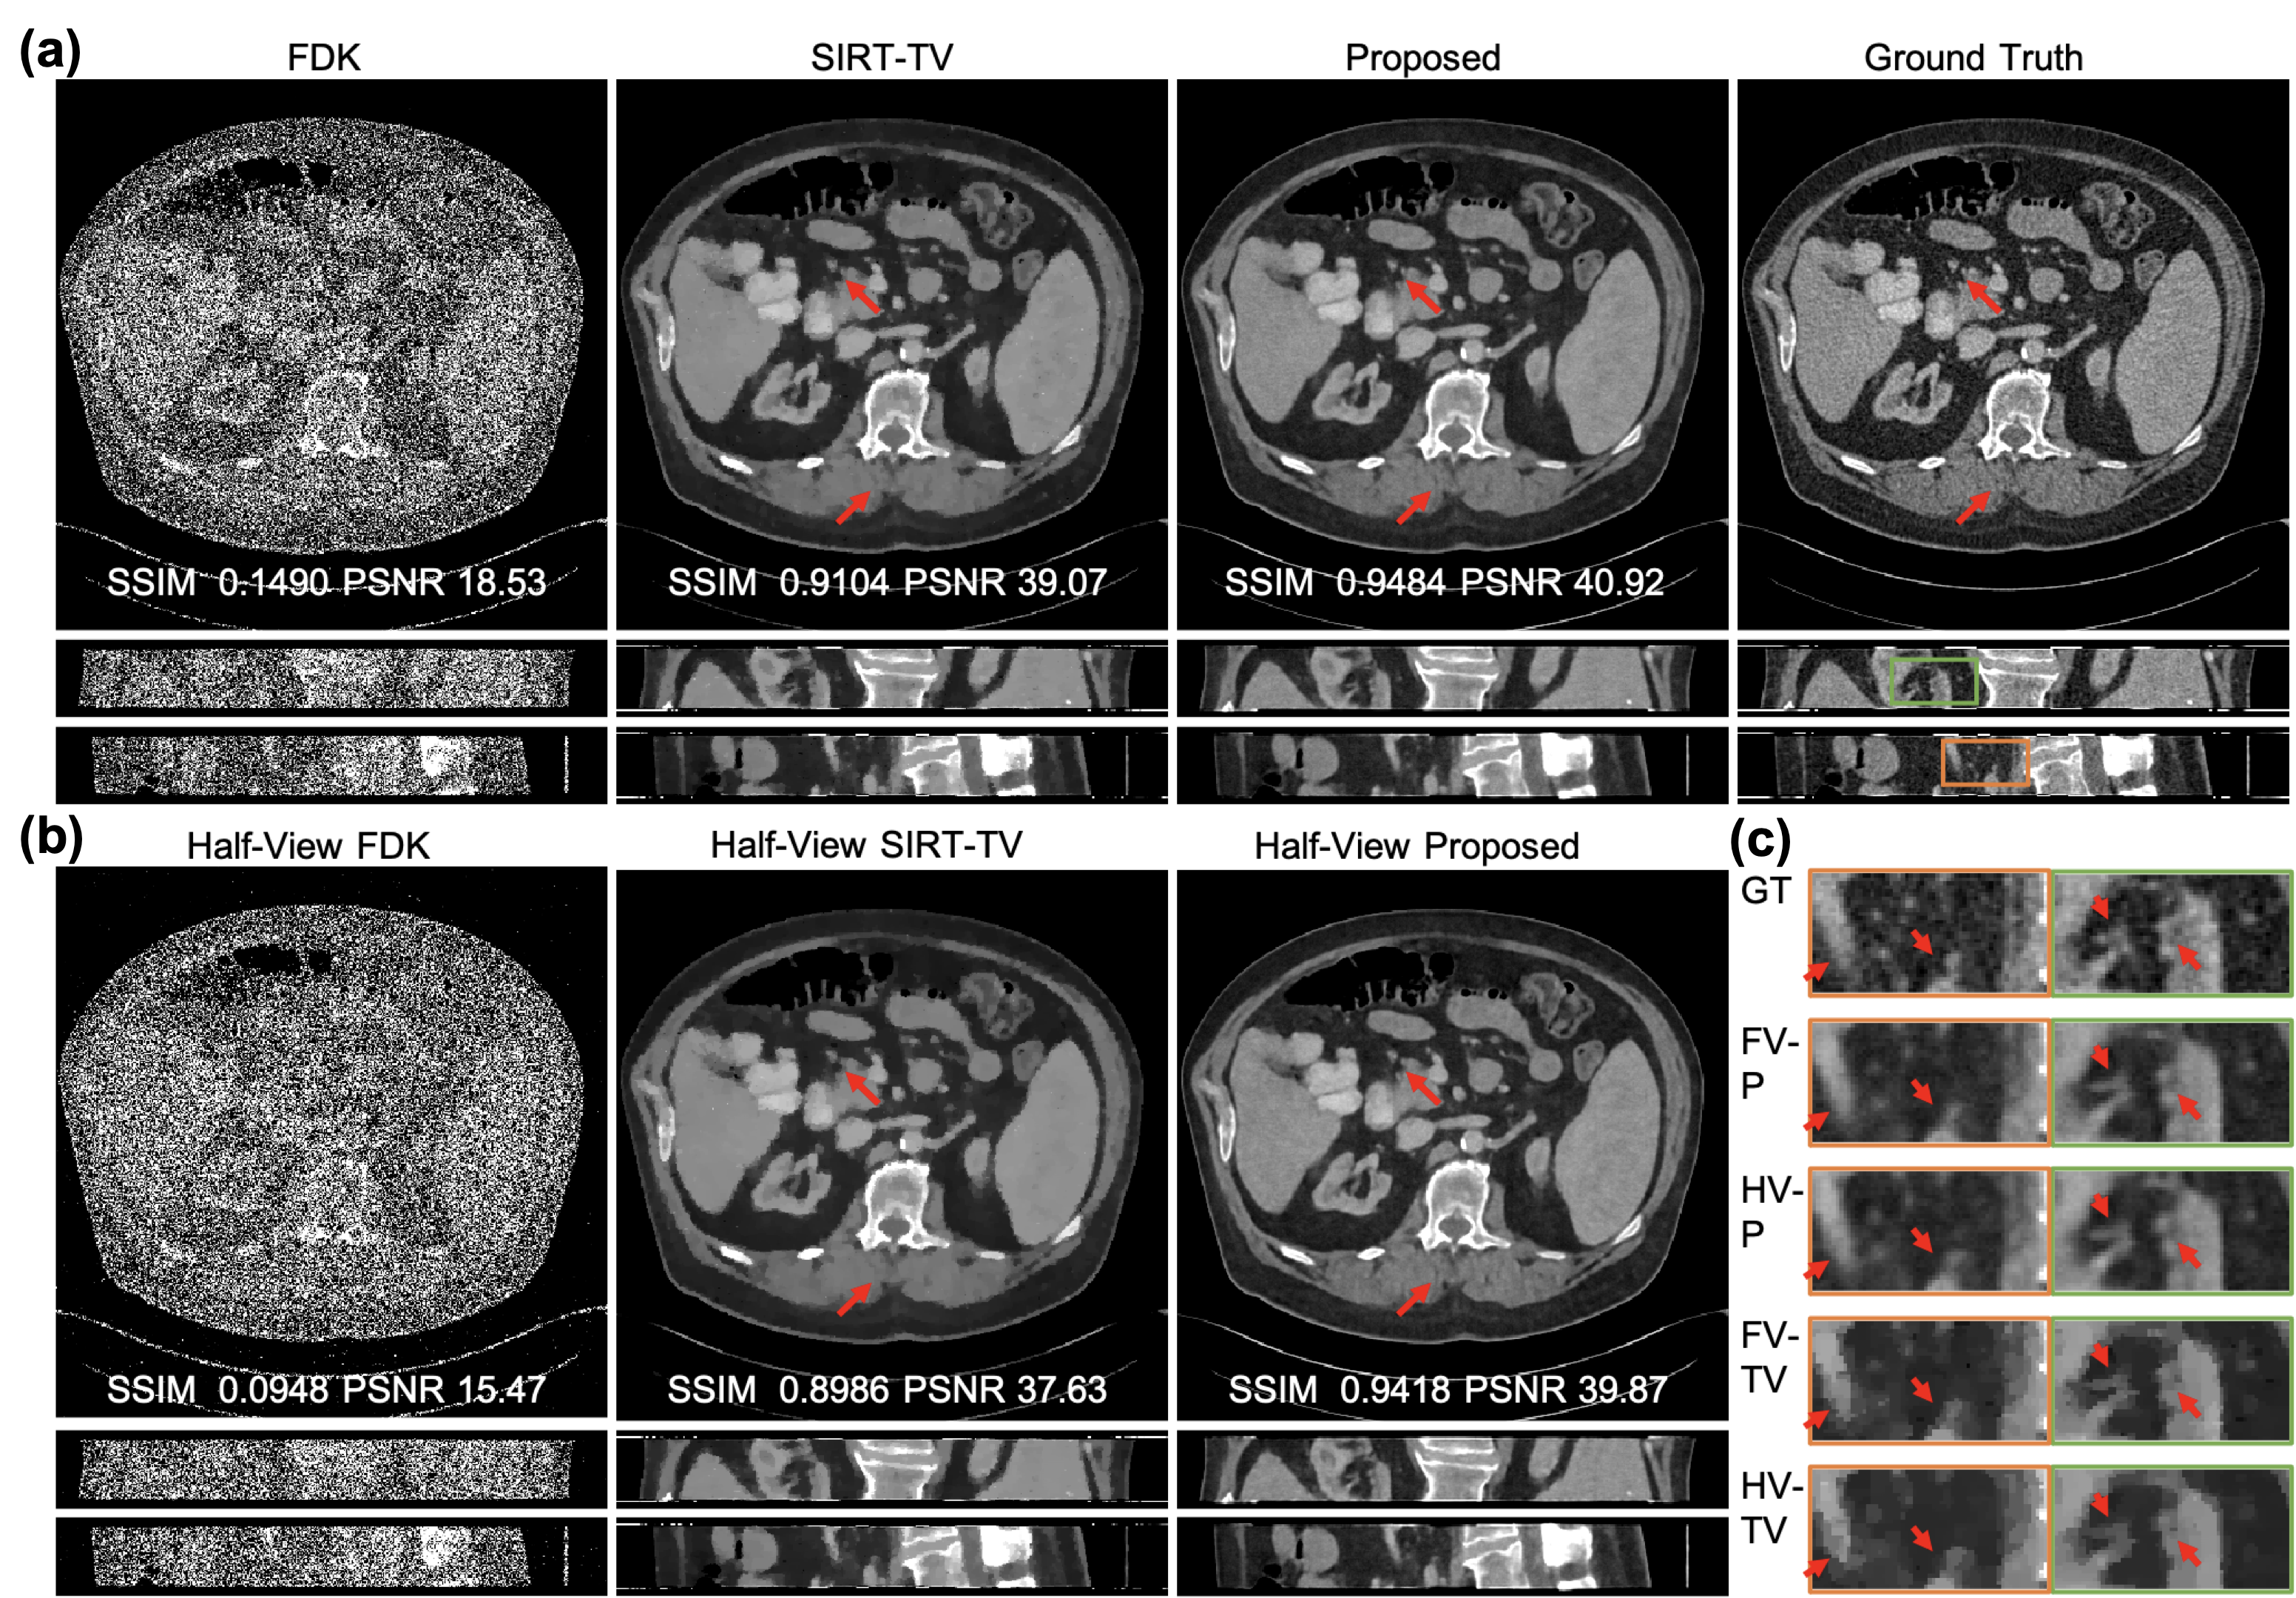

Representative full-view and half-view reconstructions are shown in Fig. 5. The fine details indicated by the red arrows are successfully restored with our methods for both full-view and half-view cases while missing structures or distortions are observed with the SIRT-TV particularly in the half-view scenario. Additionally, unnatural waxiness is also observed in the zoom-in regions of SIRT-TV results. Moreover, our half-view reconstruction scores are even better than the full-view reconstruction with the conventional method in terms of structural similarity index metric (SSIM) and peak signal-to-noise ratio (PSNR) metric, demonstrating the superiority of our method. More importantly, our method demonstrates impressive stable performance despite significant acquisition condition change from full-view to half-view (<1.0%absentpercent1.0<1.0\% loss in SSIM and <4.0%absentpercent4.0<4.0\% loss in PSNR), which is even more robust than the classic SIRT-TV.

Refer to caption

Figure 5: Representative images reconstructed using competing methods on simulated data. (a) The full-view reconstructions with FDK, SIRT-TV, and our method displayed against the ground truth, with exemplary axial, coronal, and sagittal views included from top to bottom; (b) the reconstructions from halved views; and (c) magnified regions from the coronal and sagittal views as indicated by the green and orange boxes respectively and displayed in the descent order of image sharpness and structural fidelity: ground truth (GT), our full-view and half-view reconstructions (FV-P, HV-P), and full-view and half-view reconstructions with SIRT-TV (FV-TV, HV-TV) from top to bottom. The display window is W/L:400/50 HU. The red arrows indicate the structural details are easy to recover for our methods but challenging for SIRT-TV.